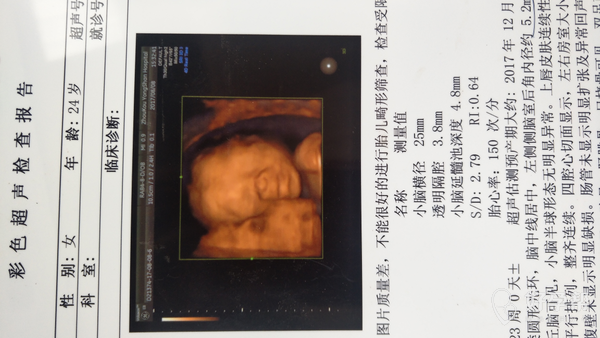

你好,四维B超报告,宝宝基本正常,羊水正常,胎盘正常,脑室这个宽度目前这个月份问题不大,28-30周以后复查,这个时候大部分吸收。24到28周糖耐量筛查,排除妊娠糖尿病。祝好运,记得点击采纳。